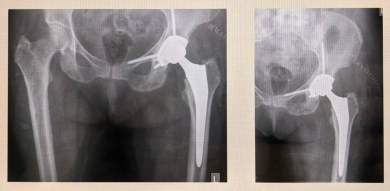

Обследование выявило в вертлужной впадине костный дефект – расшатывание компонента эндопротеза, установленного ранее.

«Мы удалили старый эндопротез и провели санацию с установкой временного эндопротеза с антибиотиком, купировав воспаление. Затем удалили временный эндопротеза и сделали повторное эндопротезирование сустава с установкой укрепляющей конструкции и костной пластикой дефекта вертлужной впадины. Учитывая сложную конфигурацию дефекта, была рассчитана и выполнена индивидуальная укрепляющая конструкция посредством применения 3D-принтинга. Такой метод применяется для пациентов с застарелыми повреждениями и посттравматическими костными дефектами», – рассказал заведующий отделением травматологии и ортопедии МОНИКИ Евгений Степанов.